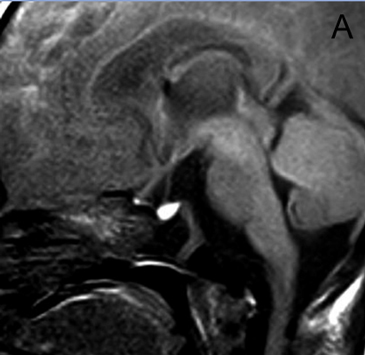

Figura 4A. Corte sagital, secuencia T1w. Glándula pituitaria normal en adulto joven (27 años), muestra foco posterior de hiperseñal de la neurohipófisis (punta de flecha); la señal de la adenohipófisis es similar a la de la protuberancia.

Figura 4B. Corte sagital, secuencia T2w.en el mismo paciente, la glándula pituitaria, muestra la neurohipófisis con leve hiperseñal (punta de flecha); la señal de la adenohipófisis es también similar a la protuberancia en esta secuencia.

Figura 4C. Corte sagital, secuencia T1w post inyección de Gadolinio. La glándula pituitaria, muestra refuerzo normal incluyendo el tallo pituitario; en el cerebro solo se refuerzan las estructuras vasculares.